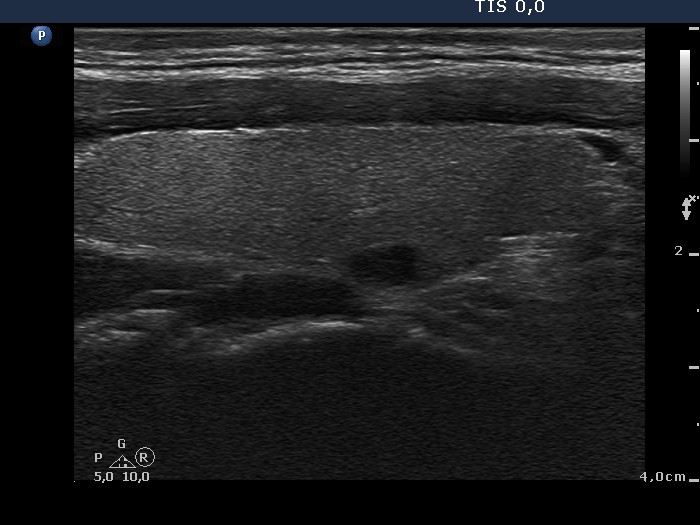

The borders of the nodule - case conp 034 (ultrasonographic picture 2)

Right lobe, longitudinal scan

Right lobe, longitudinal scan. The lesion in the dorsal part shares practically no nocological significance.